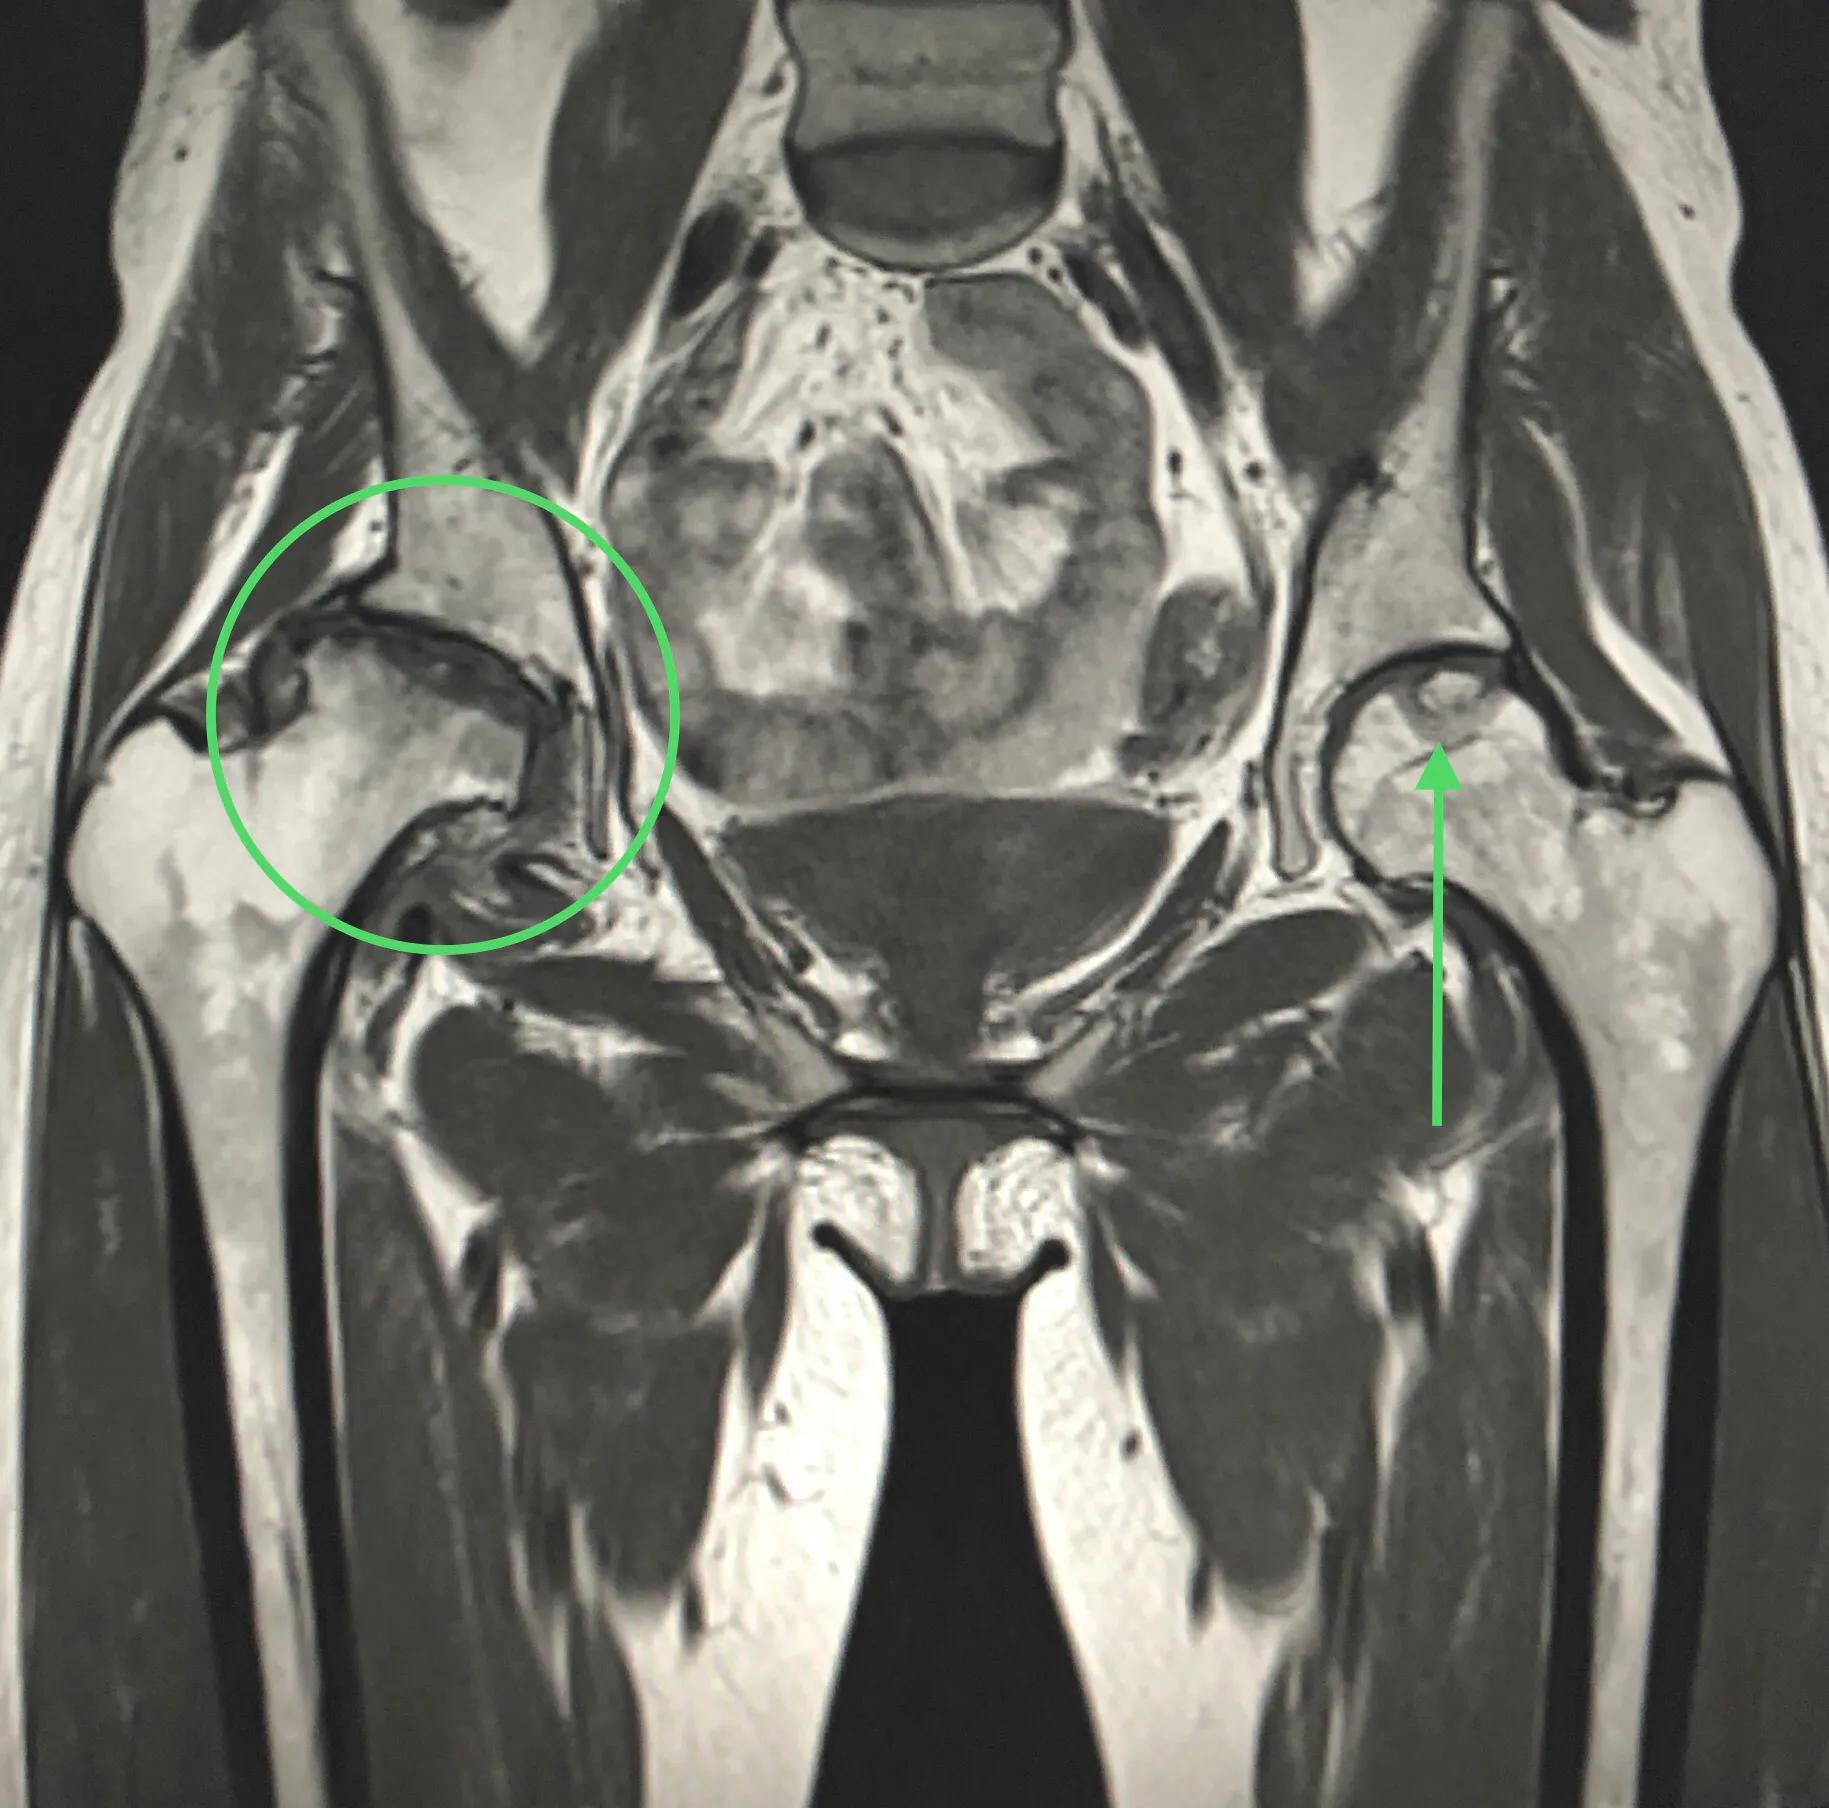

图6: MRI。右侧股骨头坏死4期,圆圈示。已完全失去股骨头形态。左侧股骨头坏死1期(很早期)。